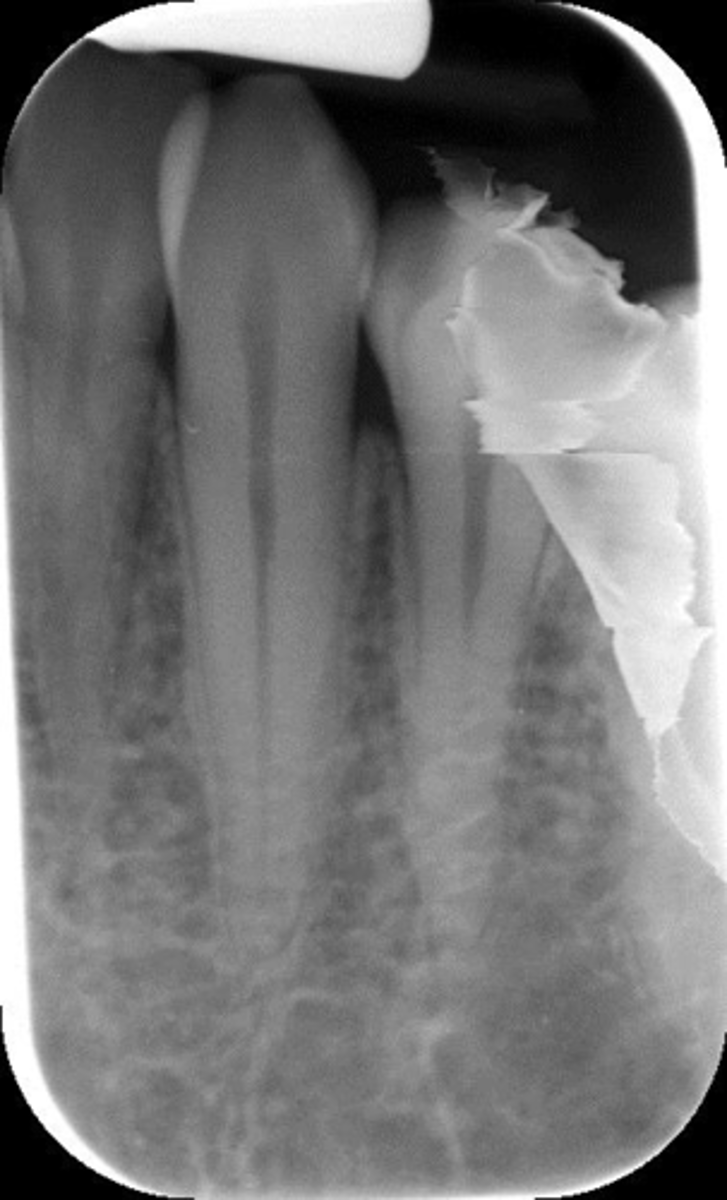

Elongated, vertical angulation, film holder (metal bar)

What is this error?

Rinn instrument bar, vertical angulation